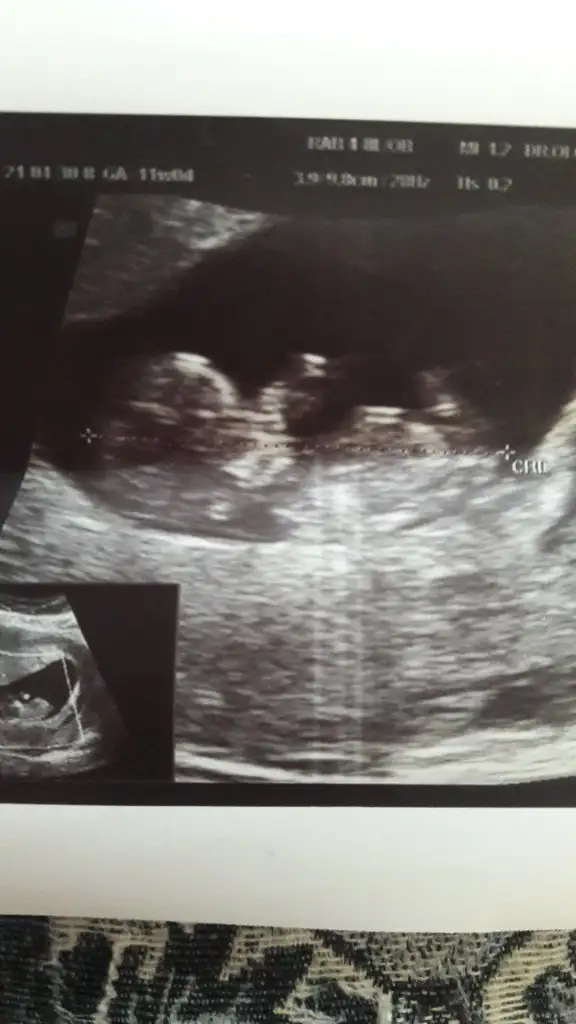

Canım bizede 12+5 de tahminde bulunurmusun karından usd dr bir tahminde bulundu ama net değil dedi🤗

Eklentiler

• image.webp

image.webp

16 KB · Görüntüleme: 63